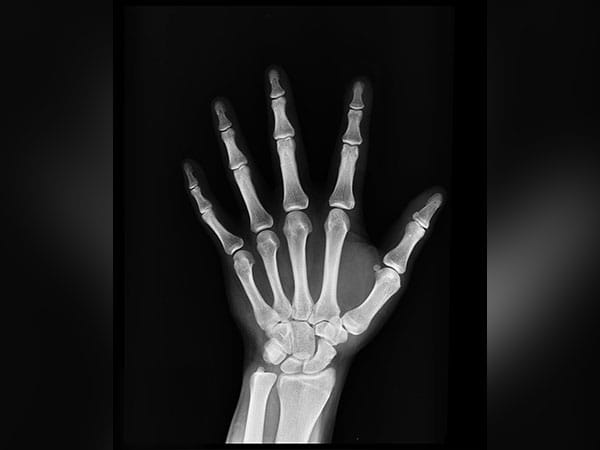

As a fracture heals, it progresses through various stages. These include clotted blood forming at the fracture, which becomes replaced by a callus of fibrous tissues and cartilage, followed by formation of a hard bony callus. The bone is then remodeled, as regular bone replaces the hard callus and the bone returns to its usual shape.

The team was able to observe the CD73-positive MSCs moving towards the site of the fracture and forming new cartilage and bone cells to heal the fracture. The CD73-positive sECs were also involved in the healing of the fracture, as they contributed to the process of ‘neovascularisation’, the formation of new blood vessels to support the healed bone.

Finally, they went on to graft CD73-positive MSCs into the area of a fracture, which markedly enhanced the healing process compared with when they grafted into CD73-negative MSCs.